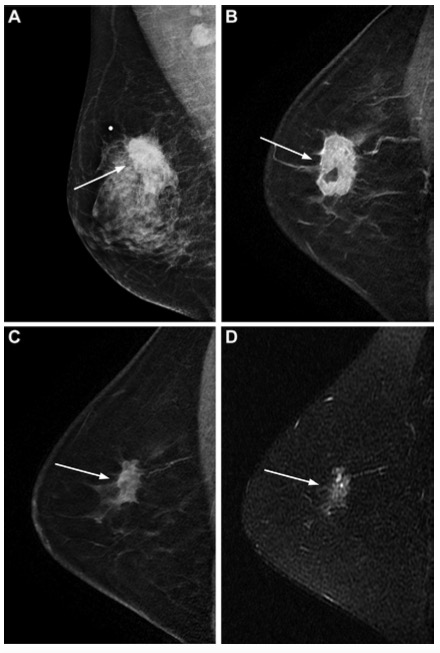

圖 一個被預測模型分層為低風險患者的代表圖像。一位54歲的女性,臨床上患有T3N2 Luminal型乳腺癌,在保乳手術和腋窩淋巴結清掃前接受了四個周期的多柔比星加環磷酰胺治療,隨后又接受了四個周期的多西他賽。手術組織病理學檢查顯示,殘留的1厘米浸潤性導管癌沒有淋巴管浸潤,14個切除的結中有兩個淋巴結轉移。患者接受了輔助性的放射治療和輔助性的內分泌治療。(A)新輔助化療(NAC)前的乳房內側斜位檢查顯示一個不規則的腫塊,沒有微鈣化(箭頭)。新輔助化療前和新輔助化療后的矢狀位增強T1加權MRI掃描(B)顯示一個不規則形腫塊(箭頭)。(D)NAC后矢狀面T2加權MRI顯示一個不規則形腫塊(箭頭),沒有瘤周水腫。該患者被歸類為低風險(遠處轉移15分,死亡18分),遠處轉移(54歲0分+臨床N2期5分+無淋巴管侵犯0分+無瘤周水腫0分=5分)和死亡(54歲0分+臨床T3期5分+無微鈣化0分+無瘤周水腫0分=5分)分別得分為5分。術后10年,患者仍然存活,沒有遠處轉移